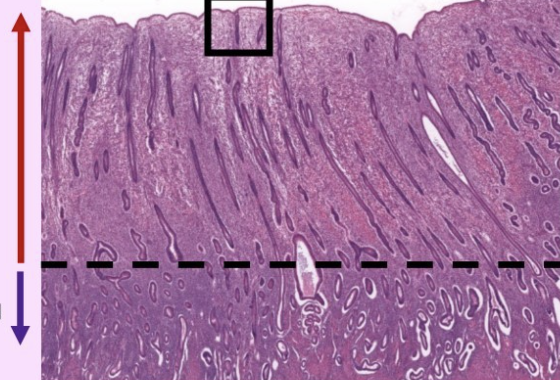

what is this slide

top = stratum functionale

bottom = stratum basale

endometrium of uterus